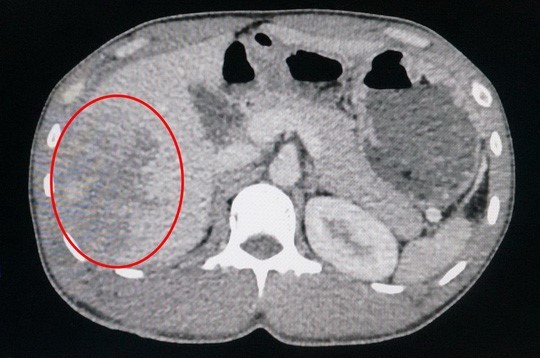

Vùng gan tổn thương sau tai nạn hy hữu của nạn nhân. |

Kết quả cận lâm sàng cho thấy bệnh nhân bị vỡ gan phức tạp, chảy máu trong đầy ổ bụng. Ngay lập tức, các bác sĩ đã phẫu thuật khẩn cấp, mở ổ bụng khâu cầm máu gan, rửa sạch, đặt dẫn lưu… cứu bệnh nhân. Hiện sức khỏe anh Tình đã ổn định.